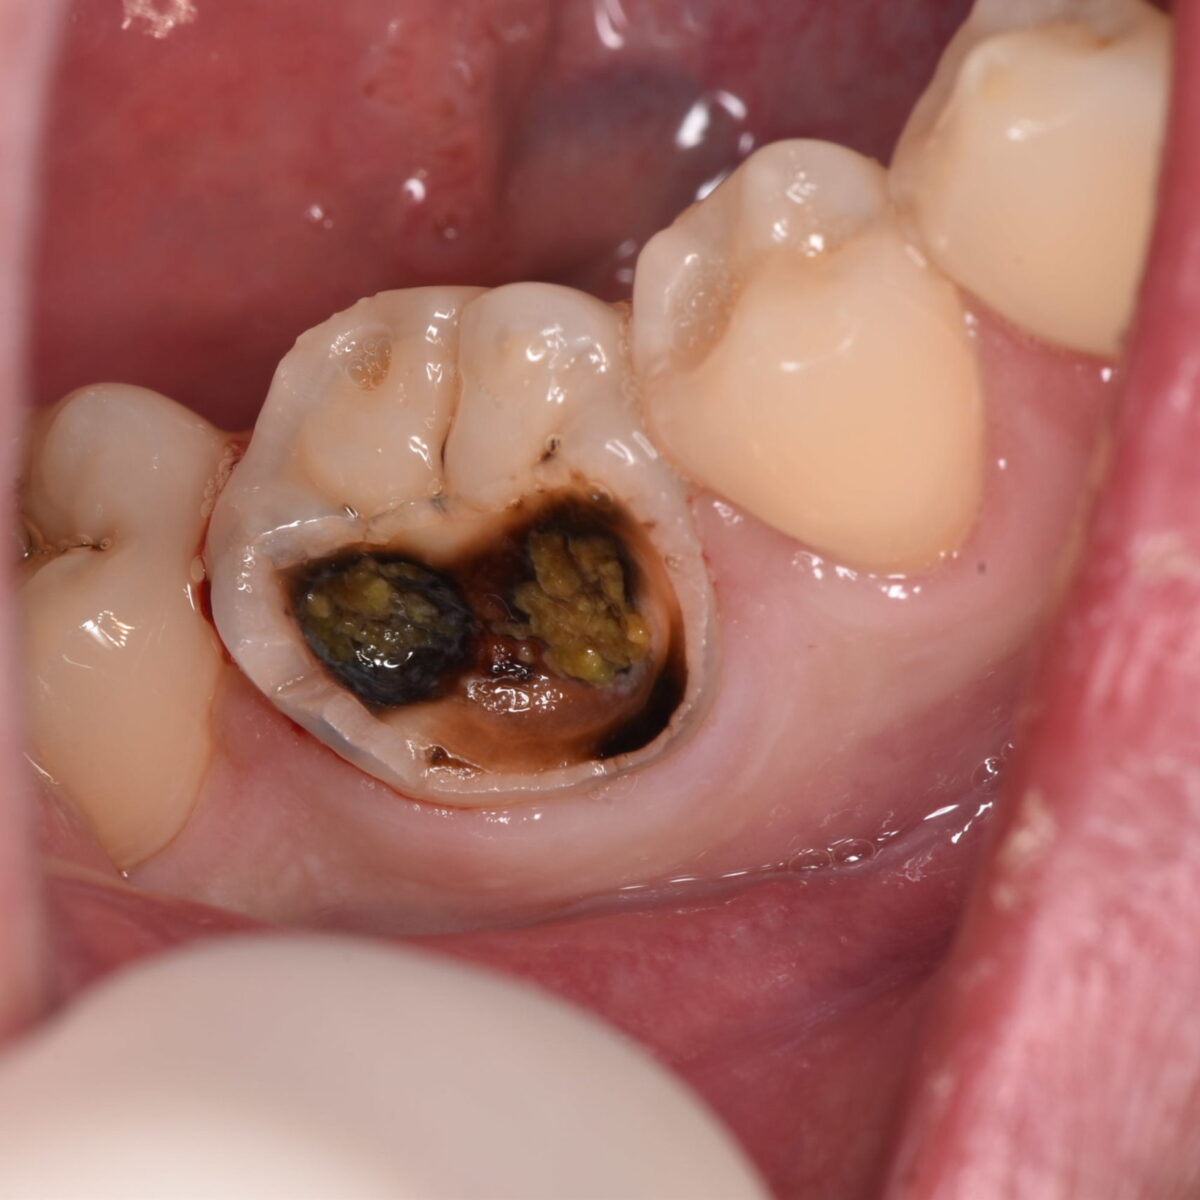

銀歯の下、20年

【東京メトロ東西線妙典駅 徒歩5分の歯医者】市川、妙典の歯科医院、めぐりデンタルクリニックの梶原です。 今回は20年物の銀歯を外したので、その話。20年物はなかなかないですね。ちょ…